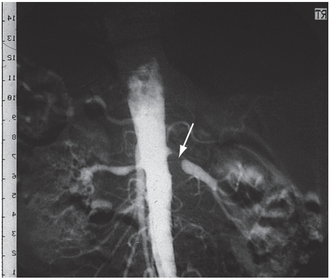

944 What potential cause of HT does this angiograph show? Digital subtraction angiography, showing typical unilateral atheromatous renal artery stenosis with post-stenotic dilatation (arrow). K & C.